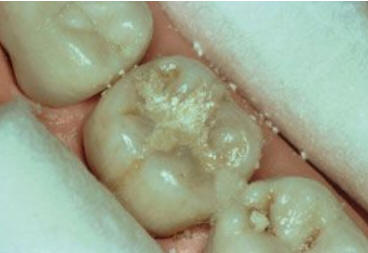

Una morfología de la fisura estrecha, con forma de botella de "Coca-Cola" genera un nicho ecológico ideal para la colonización de cualquier bacteria productora de ácidos. Al no poder remover en forma períodica dicho biofilm de una zona tan estrecha, el ataque ácido genera una lesión cariosa en la dentina, con un aspecto de esmalte intacto a la inspección visual, o sea un típico código 3 y 4 de ICDAS Completo. (Caries Moderada para el ICDAS COMBINADO)

Código 3 (Caries moderada) in vitro. Los códigos 3 in vivo debe ser sellado para evitar el avance del proceso carioso. (MNO)

Código 4 (Caries moderada) in vitro. Los códigos 4 in vivo deben ser tratados en forma operatoria con preservación dental (MOPD), porque presentan dentina infectada.